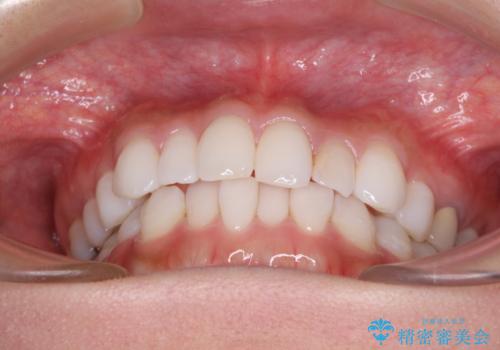

軽度の叢生をインビザライン・ライトで解消

- 前歯が気になるとのことで来院された患者様です。

歯列不正は軽微であったため、インビザライン・ライトにより、費用を抑えて矯正治療を行うこととしました。

短期間で気になる前歯の歯列を改善することができました。